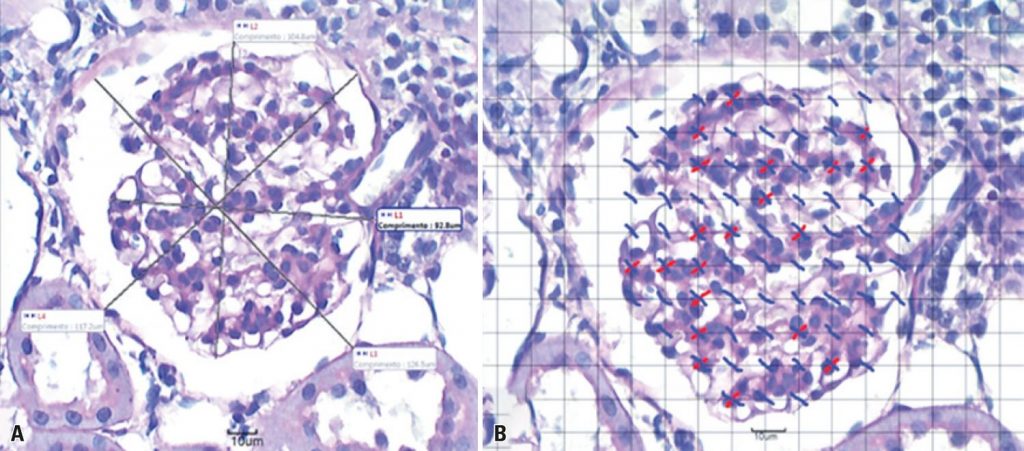

Após a exposição dos animais do Grupo Tabagista, observou-se menor ganho de peso; menor consumo de água e ração; menor peso, diâmetro e volume renal; redução em espessura cortical e densidade de volume glomerular; diminuição no diâmetro glomerular e capsular; aumento na densidade mesangial; volume urinário diminuído; níveis aumentados de glicose, creatinina sérica e microalbuminúria; níveis reduzidos de creatinina urinária e redução da taxa de depuração da creatinina.